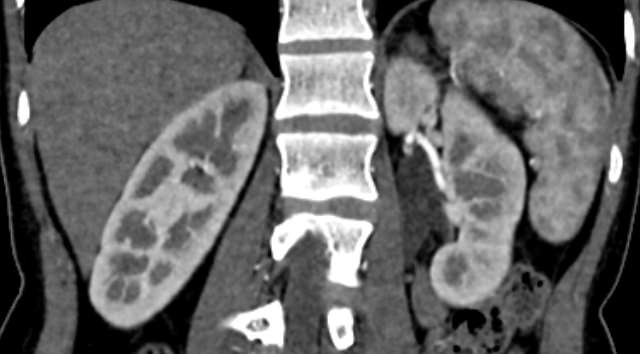

Мультиспиральная КТ сосудов почек (КТ-ангиография) с внутривенным болюсным контрастированием проводится для диагностики патологии почечных артерий. С помощью КТ-ангиографии можно выявить врожденные аномалии развития сосудов почек, диагностировать стенозы (уменьшение просвета) почечных артерий за счет развития атеросклеротических бляшек.

КТ сосудов почек применяется для выявления признаков вторичной артериальной гипертензии, при планировании оперативных вмешательств и для оценки успешности проведенной операции на сосудах. КТ ангиография почечных артерий позволяет оценить их анатомию, выявить добавочные и аберрантные почечные сосуды, определить типично ли они распространяются в ворота почки или заходят в паренхиму через корковый слой.

Ангиография почечных артерий может показать наличие:

• аневризмы (расширение  артерии);

• аномальных связей между артерией и веной (фистула или свищ);

• тромбов (сгустки крови) в просвете артерий;

• сужения кровеносных сосудов почек (почечный стеноз);

• доброкачественных или злокачественных опухолей;

• активного кровотечения из почки.

• острую артериальную окклюзию почки (инфаркт почки);

• заболевание почки в результате атероэмболии;

• количество добавочных почечных артерий и варианты их отхождения